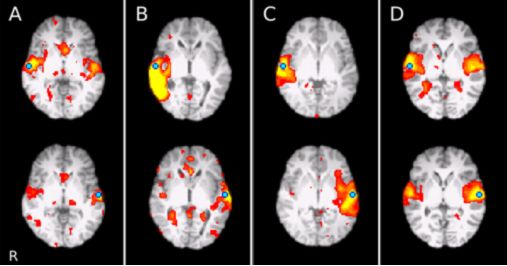

5.基于血池显像剂(纳米氧化铁)的高分辨率3D容积增强磁共振在儿童脑动静脉畸形诊疗中的应用研究

High-resolution 3D volumetric contrast-enhanced MR angiography with a blood pool agent (ferumoxytol) for diagnostic evaluation of pediatric brain arteriovenous malformations.

DOI: 10.3171/2018.3.PEDS17723.

动静脉畸形(AVMs)患者常常需要反复行MRI或MRA、CTA和DSA等检查。理想的成像方式既可以提供良好的血管成像,又不额外增加风险,如辐射线暴露。本研究的目的是使用高分辨率3D容积序列纳米氧化铁增强MRA(fe-SPGR),通过与CTA和DSA比较,评价其在儿童AVM可视化和评分中的作用。作者回顾性研究了2014年4月至2017年8月期间的21例AVM患者,均使用fe-SPGR, CTA和DSA来评估病情。两位经验丰富的评分人员利用Spetzler-Martin评分标准对所有的AVM进行评分。采用5点李克特量表评估病灶显著性(Lesion conspicuity,LC)和诊断可靠性(diagnostic confidence,DC),并确定评价者的一致性。关于AVM的Spetzler-Martin评分,上述三种检查方法未见显著差异;fe-SPGR的LC和DC评分高于CTA;CTA和fe-SPGR,CTA和DSA之间的LC评分有显著差异,而fe-SPGR和DSA之间的LC评分无差异。DSA, fe-SPGR和CTA三者间以及两两比较,DC评分均有明显差异。评分者的一致性在所有检查方法中均表现良好。作者认为Fe-SPGR在脑AVMs诊断评价中表现良好,其影像效果优于CTA,其Spetzler-Martin分级与CTA和DSA相当。

![]()

右侧额叶AVM(A-MRA、B-CTA、C-Fe-SPGR、D-DSA)